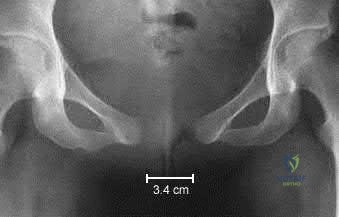

Question 9:

A 30-year-old male sustains a displaced, highly vertical (Pauwels III) femoral neck fracture following a fall from a height. What is the most appropriate surgical management for this patient to minimize the risk of nonunion and optimize biomechanical stability?

Options:

- Immediate hemiarthroplasty

- Total hip arthroplasty

- Closed reduction and percutaneous pinning with 3 parallel cannulated screws

- Open reduction and internal fixation with a sliding hip screw (DHS) or cephalomedullary nail

- Non-operative management with skeletal traction

Correct Answer: Immediate hemiarthroplasty

Explanation:

In young adults, femoral neck fractures are considered a surgical emergency to preserve the native hip joint. A Pauwels III fracture is characterized by a vertical fracture line (high shear angle), making it highly unstable. Fixation with a fixed-angle device like a sliding hip screw (often with a derotational screw) or a cephalomedullary nail offers vastly superior biomechanical stability against vertical shear forces compared to parallel cannulated screws, reducing the high risk of nonunion.